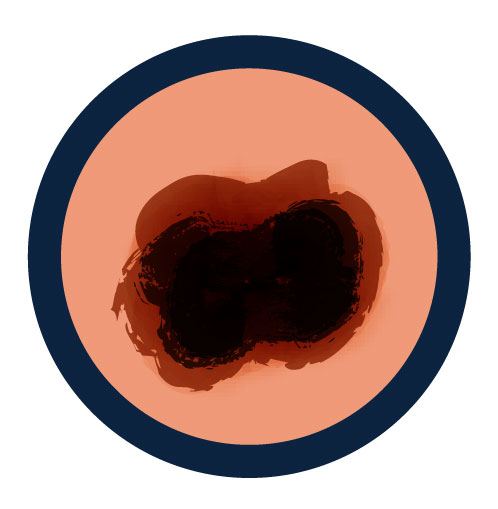

A is for Asymmetry

One half of a mole or birthmark does not match the other.

B is for Border

The edges are irregular, ragged, notched or blurred.

C is for Color

The color is not the same all over and may include different shades of brown or black, or sometimes with patches of pink, red, white, or blue.

D is for Diameter

The spot is more than 6 millimeters across (about 1/4 inch – the size of a pencil eraser), although melanomas can sometimes be smaller than this.

E is for Evolving

The mole is changing in size, shape, or color.